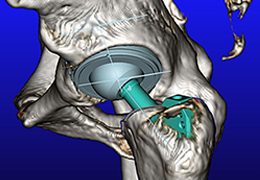

Volume Rendering

Volume rendering is performed with a very fast ray casting algorithm; lightning calculations are based on Phong-shading. Surface rendering of reconstructed surfaces is performed using OpenGL. Using texture mapping, a reconstructed surface (e.g., head or brain) may be sliced in real time, showing both surface and volume data at the same time. Initial polygon meshes serve as the basis for surface finding, cortex inflation and cortex flattening computations.

Surface Reconstruction

The surface reconstruction procedure starts with a sphere (recursively tesselated icosahedron) or a rectangle, which slowly wraps around a (segmented) volume data set. In order to avoid topological defects and to let the surface smoothly grow into deep sulci, a dynamic mesh algorithm was developed which automatically invents new polygons on the fly at places where they are needed. A reconstructed cortical surface may be inflated, cut interactively and slowly unfolded minimizing areal distortions. Statistical 3D maps may be superimposed on reconstructed, inflated or flattened cortex. Signal time courses may be invoked by simply pointing to any region of a visualized surface.